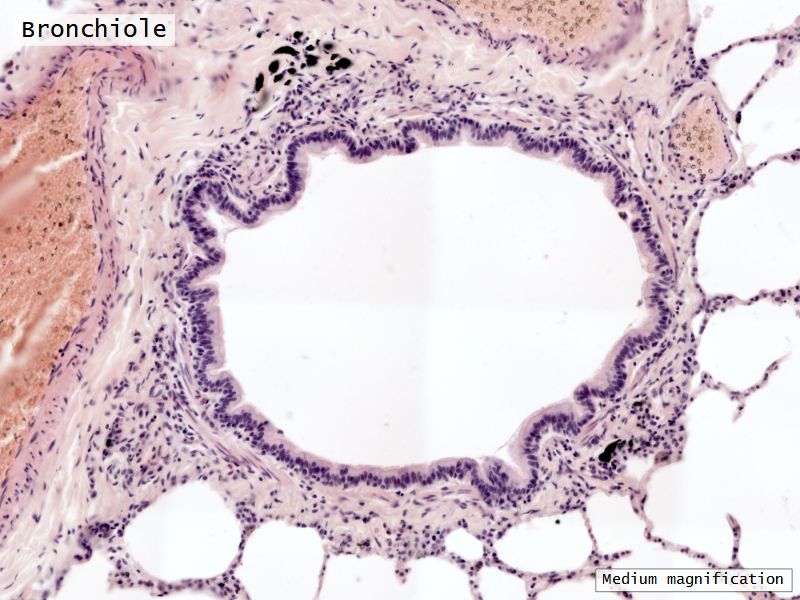

Fill in all the missing labels, and assess as you move through the slides. Answers on the down slide. It is important to do this using pen and paper, and not just glance through the images.